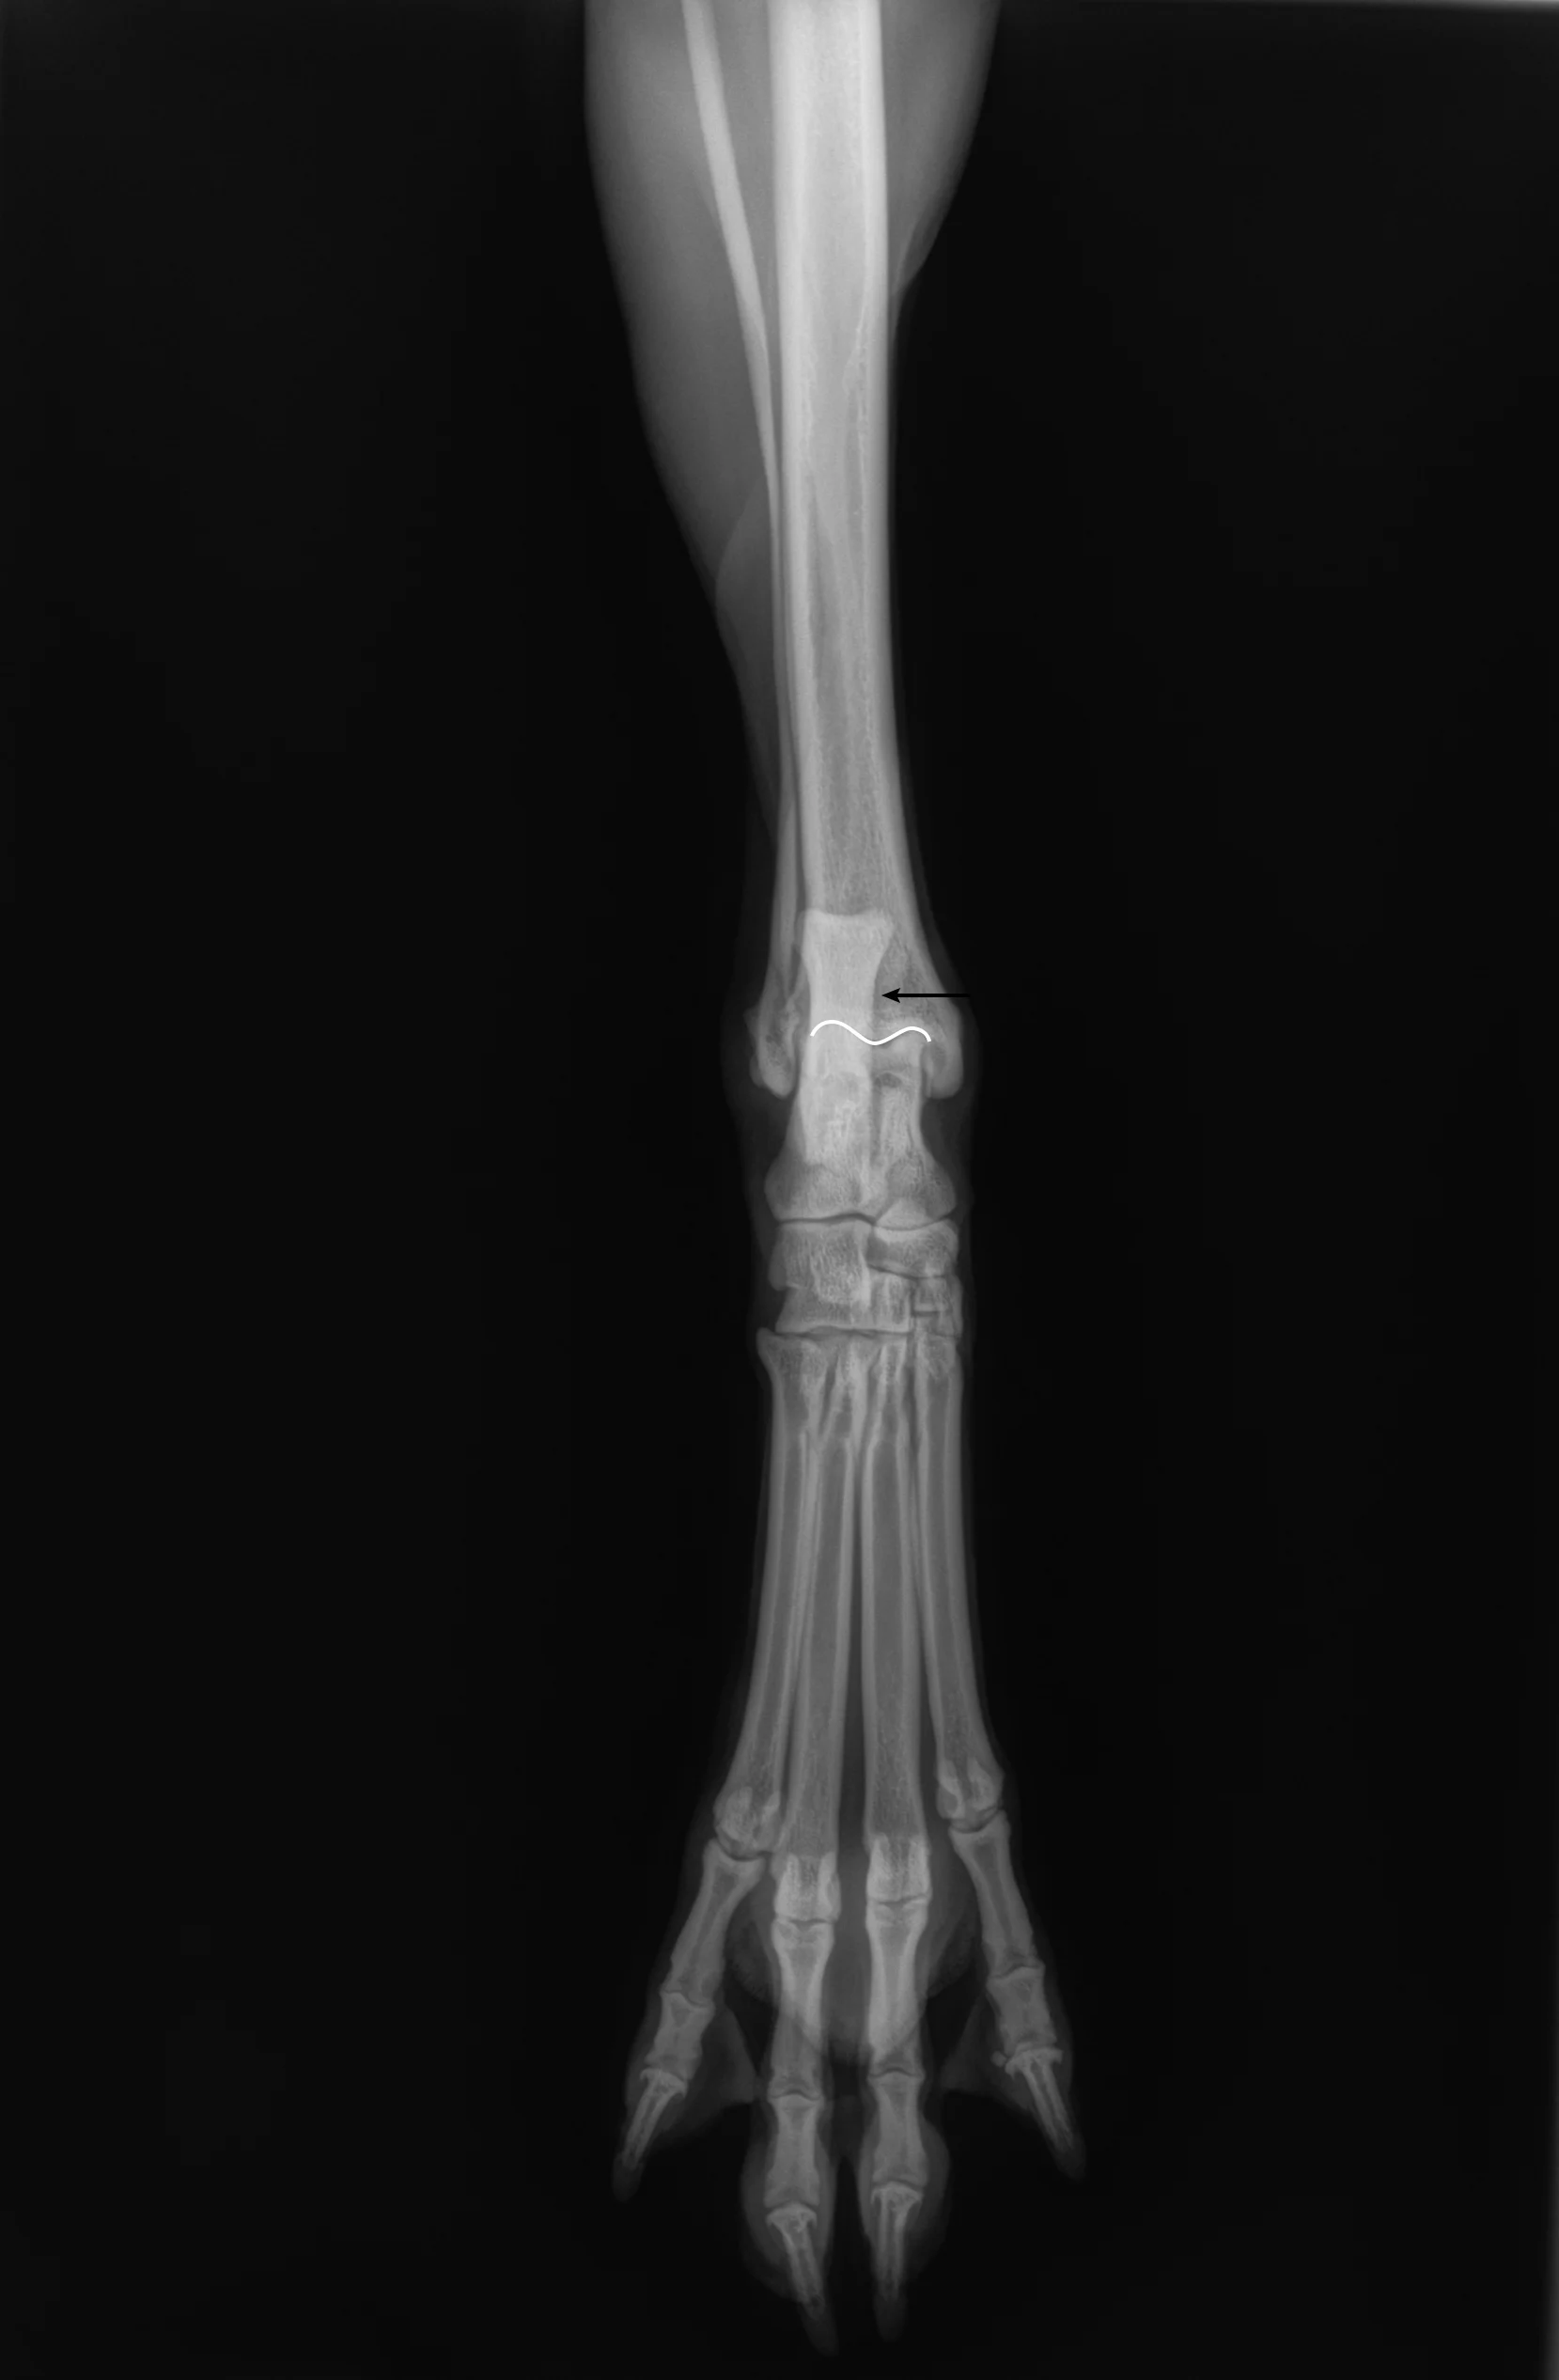

Place the patient in dorsal recumbency. Center the abdomen over a V-trough sponge positioner to keep the body straight; ensure the pelvis and caudal abdomen are outside of the trough. Position the pelvic limb with the hip, stifle, and tarsal joints fully extended. Rotate the stifle joint medially to help align the tibia and tarsus.

Step 2: Position the Beam

Center the collimator beam over the talus, which is immediately distal to the medial malleolus of the tibia and can be identified with palpation. Do not center the beam on the calcaneus, as this would point the beam proximal to the joint, which is not ideal for radiographic evaluation of the tarsus. Ensure the distal third of the tibia, fibula, and all metatarsal bones are included.

Author Insight

On the radiograph, the tarsal joint should be relaxed and not flexed, with visible space between the tarsal joints (white arrows). All metatarsal bones should be parallel to each other (gray arrows).The medial edge (dashed arrow) of the calcaneus (A) should bisect the distal intermediate ridge of the tibia (B), ensuring the tarsus and distal tibia are straight.